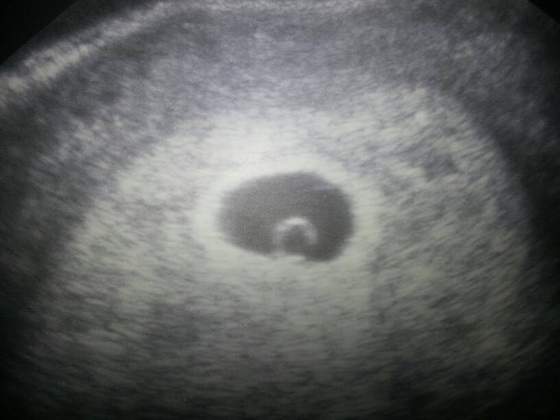

Mamusia 2013 :)